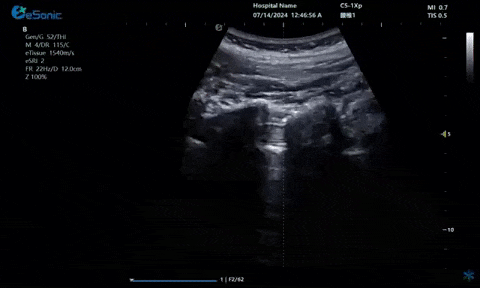

超声引导下神经根阻滞,也可以

做腰神经后支